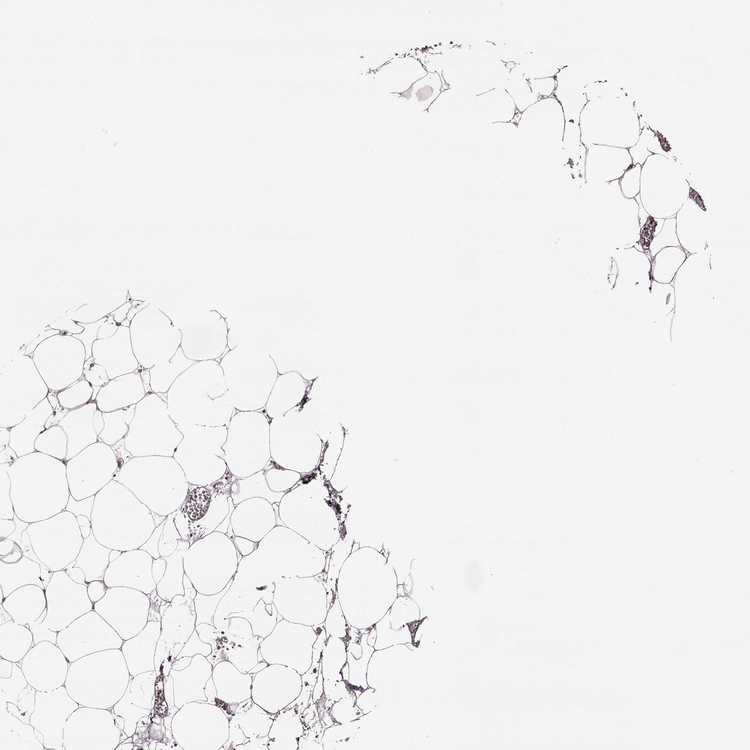

SOFT TISSUE 2 - Antibody stainingi

Antibody staining in the annotated cell types in the current human tissue is reported as not detected, low, medium, or high, based on conventional immunohistochemistry profiling in selected tissues. This score is based on the combination of the staining intensity and fraction of stained cells.

Each image is clickable and will lead to virtual microscopy that enables deeper exploration of all samples and also displays staining intensity scores, fraction scores and subcellular localization as well as patient and tissue information for each sample.

Antibody HPA054508Antibody HPA059315

Fibroblasts Not detectedNot detected

Peripheral nerve Not detectedNot detected